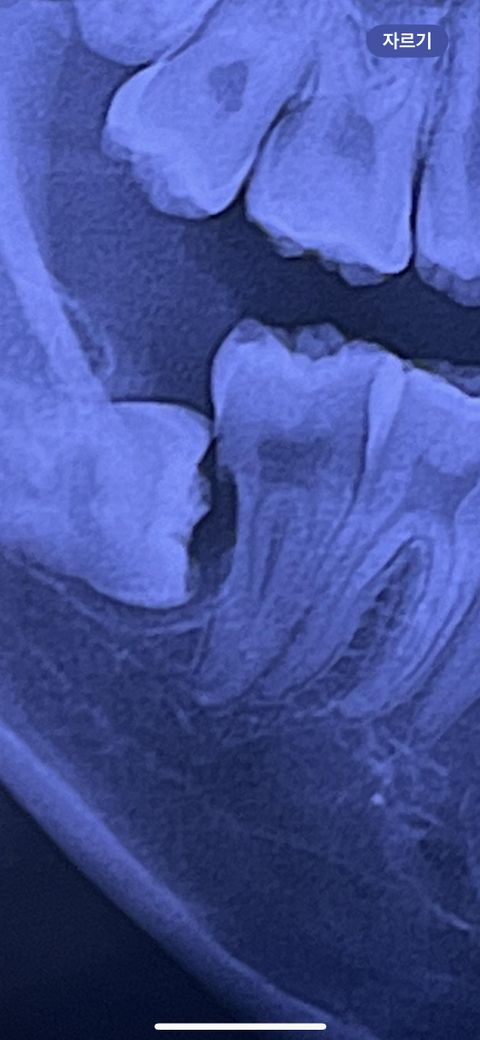

오른쪽 매복 사랑니 어금니 뿌리 흡수인가요 ?

한 달 전부터 오른쪽 어금니를 힘있게 다물면 약간의 통증이 있어서 오늘 병원에 가 사진을 찍었는데 우선 매복 사랑니가 어금니 뿌리부분을 흡수 한 경우일수도 있다고 사랑니 발치를 하고 추후 상태 보고 어금니 신경치료 이야기도 나왔는데, 사진상으로 봤을때 사랑니가 어금니를 흡수 한 경우인 것 같나요 ??

사진상으로는 사랑니 앞치아에 뿌리가 흡수된것처럼 보입니다. 일단은 사랑니 발치를 하고나서 다시 확인을 해보시는게 좋을것같습니다.

어금니 뿌리의 일부분이 녹은 것으로 보이지만 사랑니 발치 후 에 다시 사진을 찍어봐야 알 수 있습니다.

사진으로만 볼때는 앞의 치아의 뿌리부위가 흡수가 되고 있는것으로 보입니다.

사랑니로 인해서 주변조직에 문제가 발생하는 경우에는 발치를 하는것이 좋을 수 있습니다.자세한 확인을 위해 치과에서 진료를 받아보세요.

저정도 위치의 사랑니면 분명 옆 어금니에 영향을 주었을 것입니다. 사진상으로 봤을때도 옆 어금니의 뿌리가 흡수가 어느정도 된 것으로 보이나 엑스레이상 왜곡이 좀 있을 수도 있습니다.